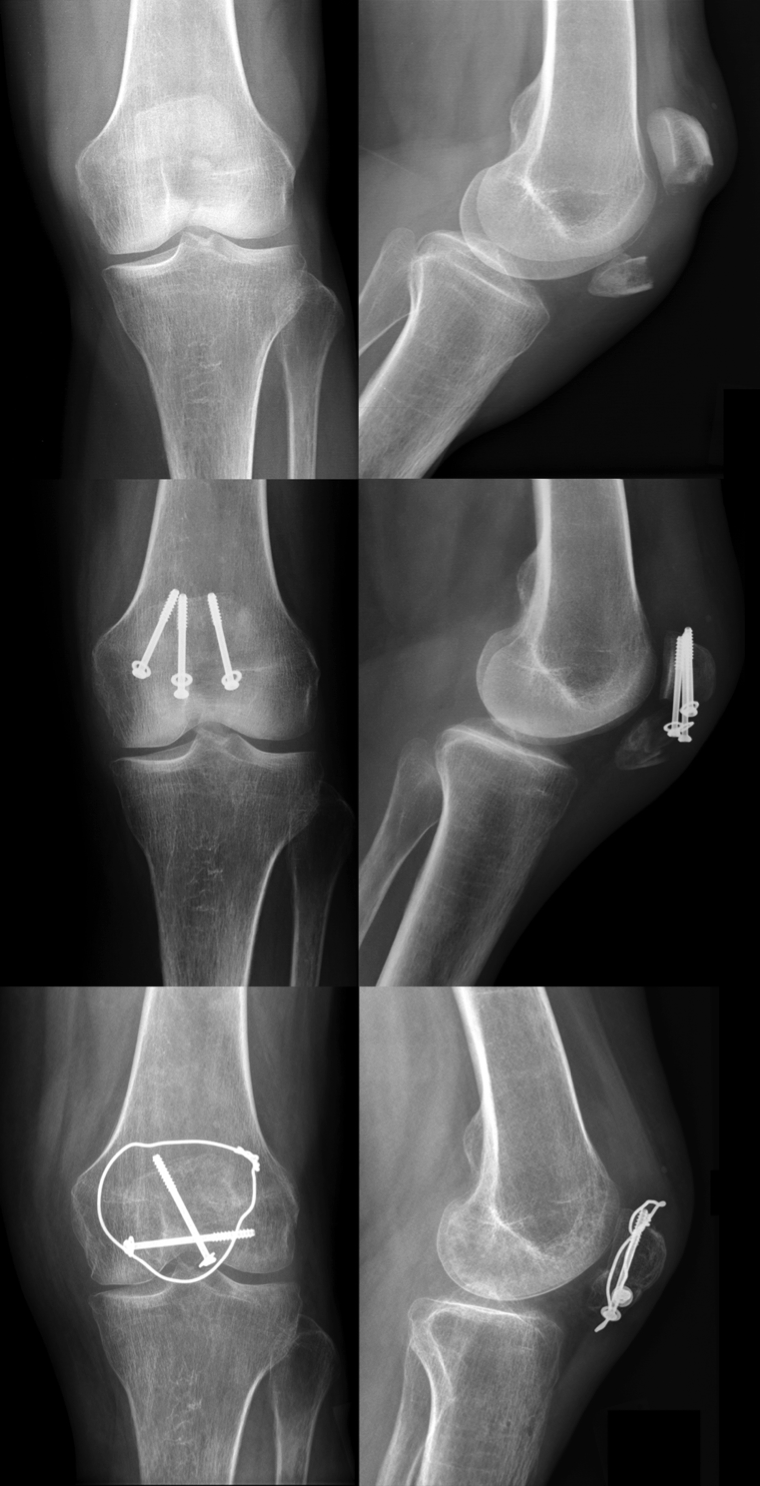

髌骨骨折术后最常见的并发症为关节活动度(ROM)下降。感染、术后长期制动及康复不当是主要诱因。在手术治疗的髌骨骨折病例中,复位丢失的发生率可达20%(图6)

图6:髌骨横向骨折术前X线片(上图)。术后3个月出现复位丢失伴螺钉拔出(中图)。翻修术后3个月采用螺钉固定联合张力带固定(下图)